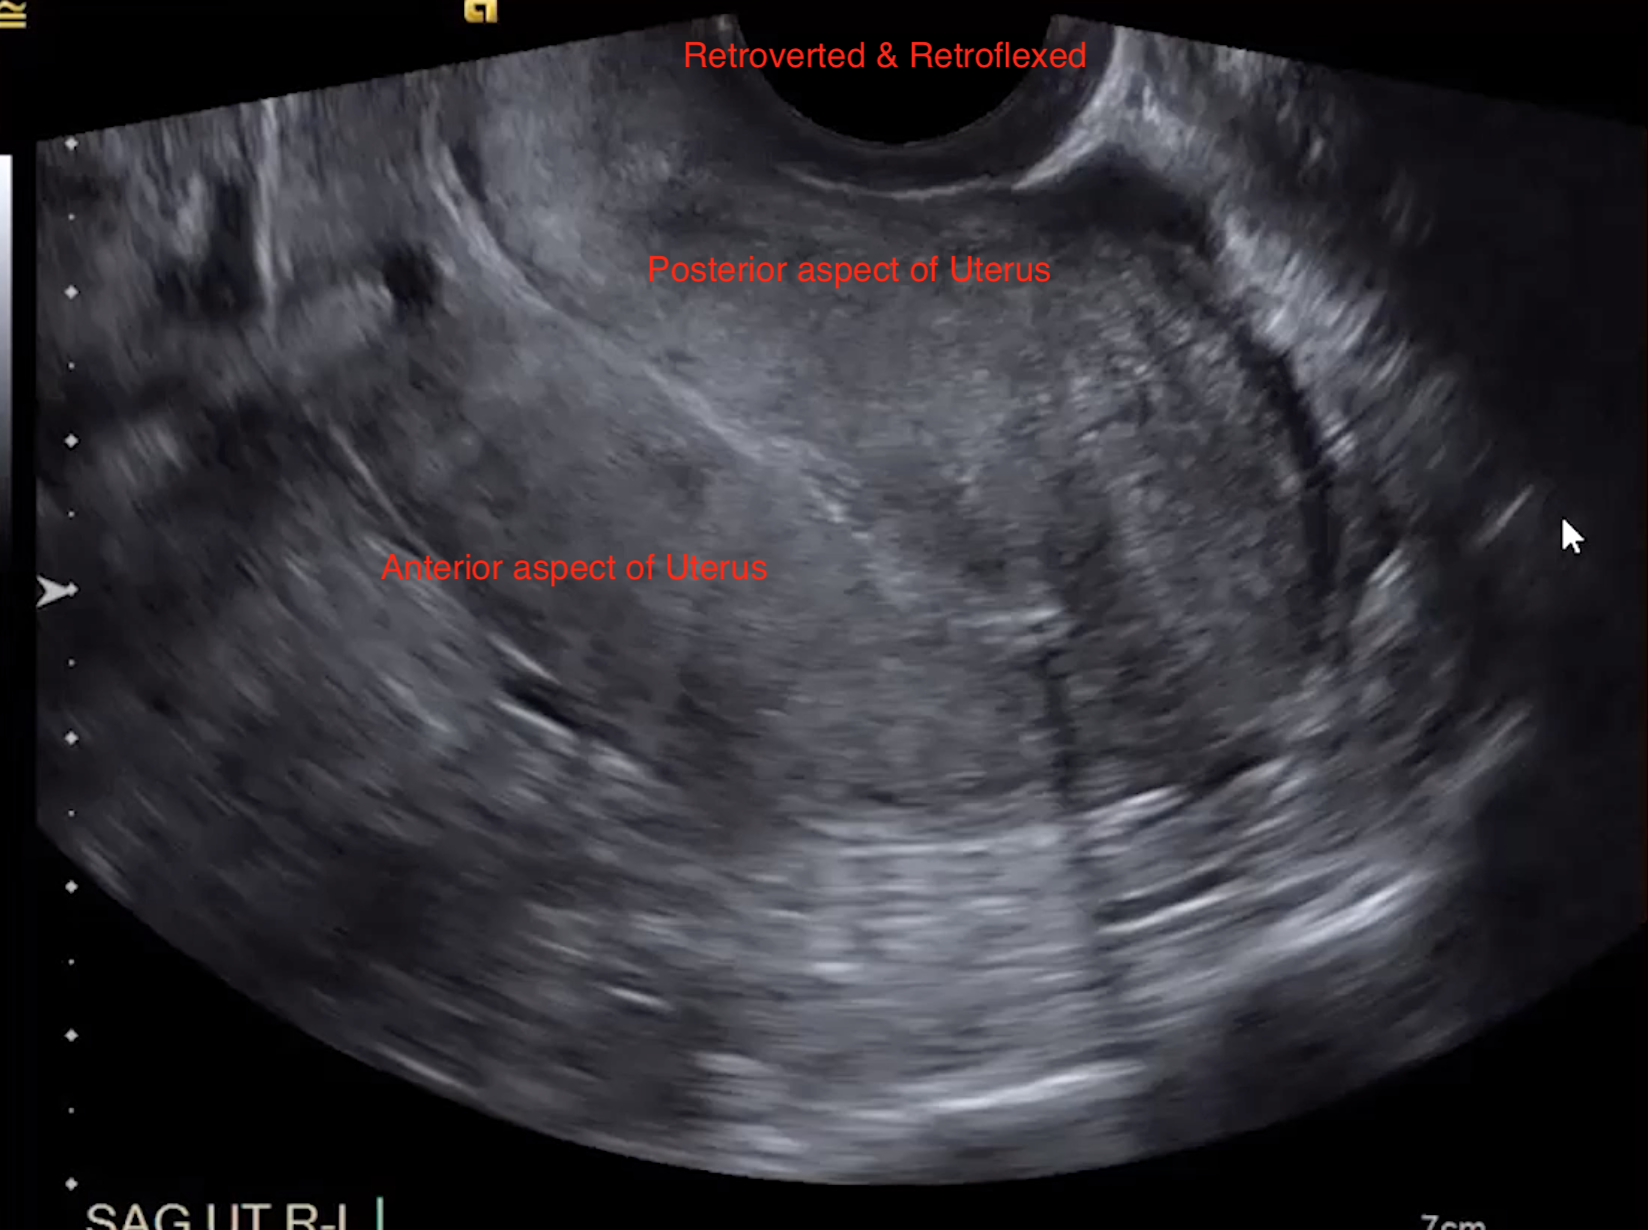

Flexion = Uterus

• Ante-flexed uterus = uterine body located anterior toward the bladder

• Retroflexed

• Uterus will look like its coming from the left side of the image (normal human left) because the prob has to be placed in the posterior fornix